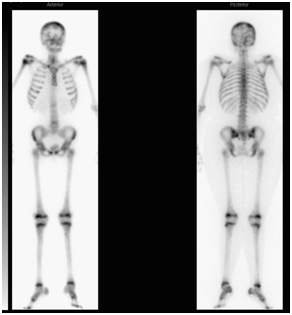

A 12-year-old Saudi girl with a known case of vitamin D deficiency and acute β-cell lymphoblastic leukemia presented to the emergency department complaining of fever, generalized bone pain for two months, and sternal prominence for one month, with no history of weight loss, masses, or swellings. On examination, she looked pale with generalized bone ache. There was a prominent sternal projection, which was not tender. No obvious lymphadenopathy or hepato-splenomegaly was detected. Further testing showed the following values: CBC: 9.59; absolute neutrophil count: 6.42; hemoglobin: 7.9; platelets: 295; Uric acid: 503 µmol/L; LDH: 754 µmol/L; Creatinine: 57 mmol/L; calcium: 2.5 mmol/L; alkaline phosphatase: 161 units/L; phosphate: 1.31 mmol/L; and potassium: 3.8 mmol/L. Her T-cell marker and myeloid markers were negative. A CT scan of the chest and abdomen displayed compression fractures extending from T1 to T6, with diffused mixed lytic and sclerotic osseous changes all over the skeleton, as shown in Figure 4. Moreover, there were multiple low attenuation lesions in the mildly enlarged kidneys. An MRI of the spine showed diffused abnormal heterogeneous appearance of the bone marrow over the entire spine and the sacrum (Figure 5), but no clear cord compression was seen. Bone scintigraphy with 99mTc-methylene diphosphonate showed diffused increase in tracer uptake in the skeleton. Patchy, geographic like elevated uptake was seen in the skull (Figure 6). The patient was on Tazocin, amikacin and voriconazole, and vitamin D 50,000 IU weekly.

Figure 6 Bone scintigraphy with 99mTc-methylene diphosphonate showing diffuse increase in tracer uptake in the skeleton and patchy, geographic like elevated uptake in the skull.

In case 2, the images showed compression fractures extending from T1 to T6, with diffused mixed lytic and sclerotic osseous changes all over the skeleton. Moreover, an MRI showed the diffused abnormal heterogeneous appearance of the bone marrow over the entire spine and the sacrum. These findings conform to what is documented in the literature and the orthopedic doctors who find such signs should suspect leukemia, which can still be diagnosed at an early stage for a good prognosis and a chance to save lives.